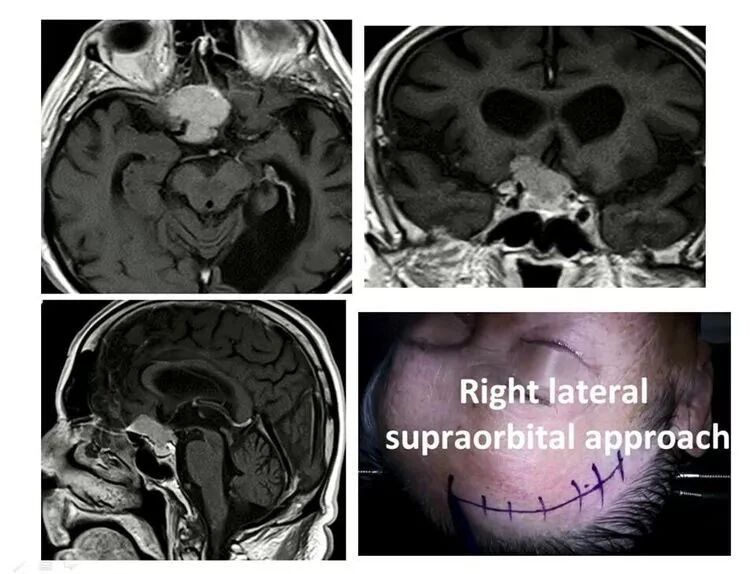

众所周知,Juha大师的标签之一,是lateral supraorbital approach。

Juha大师,运用此入路成功开展对嗅沟脑膜瘤、鞍结节脑膜瘤、颅咽管瘤、床突旁动脉瘤、前交通动脉瘤等疾病的手术治疗。

再谈Juha教授之眶上外侧入路,Lateral supraorbital approach。

应用右侧眶上外侧入路切除颅咽管瘤。术中显示,主要通过第二间隙,向外前方牵拉,分块切除肿瘤。手术堪称精美!

应用眶上外侧入路,切除此例颅咽管瘤,需注意三个特点:

其一,患者是首次手术切除,无先前不当治疗之遗害。没有经历P32内放疗,没有经历伽玛刀治疗。这样的病例,肿瘤边界粘连较轻,易于分离、牵拉。

其二,肿瘤质地较软,非坚如磐石之瘤。应学会观察CT等,综合影像评估,了解肿瘤质地。

其三,术者具有沿蛛网膜界面操作的高超本领。这样的牵拉,才相对安全。